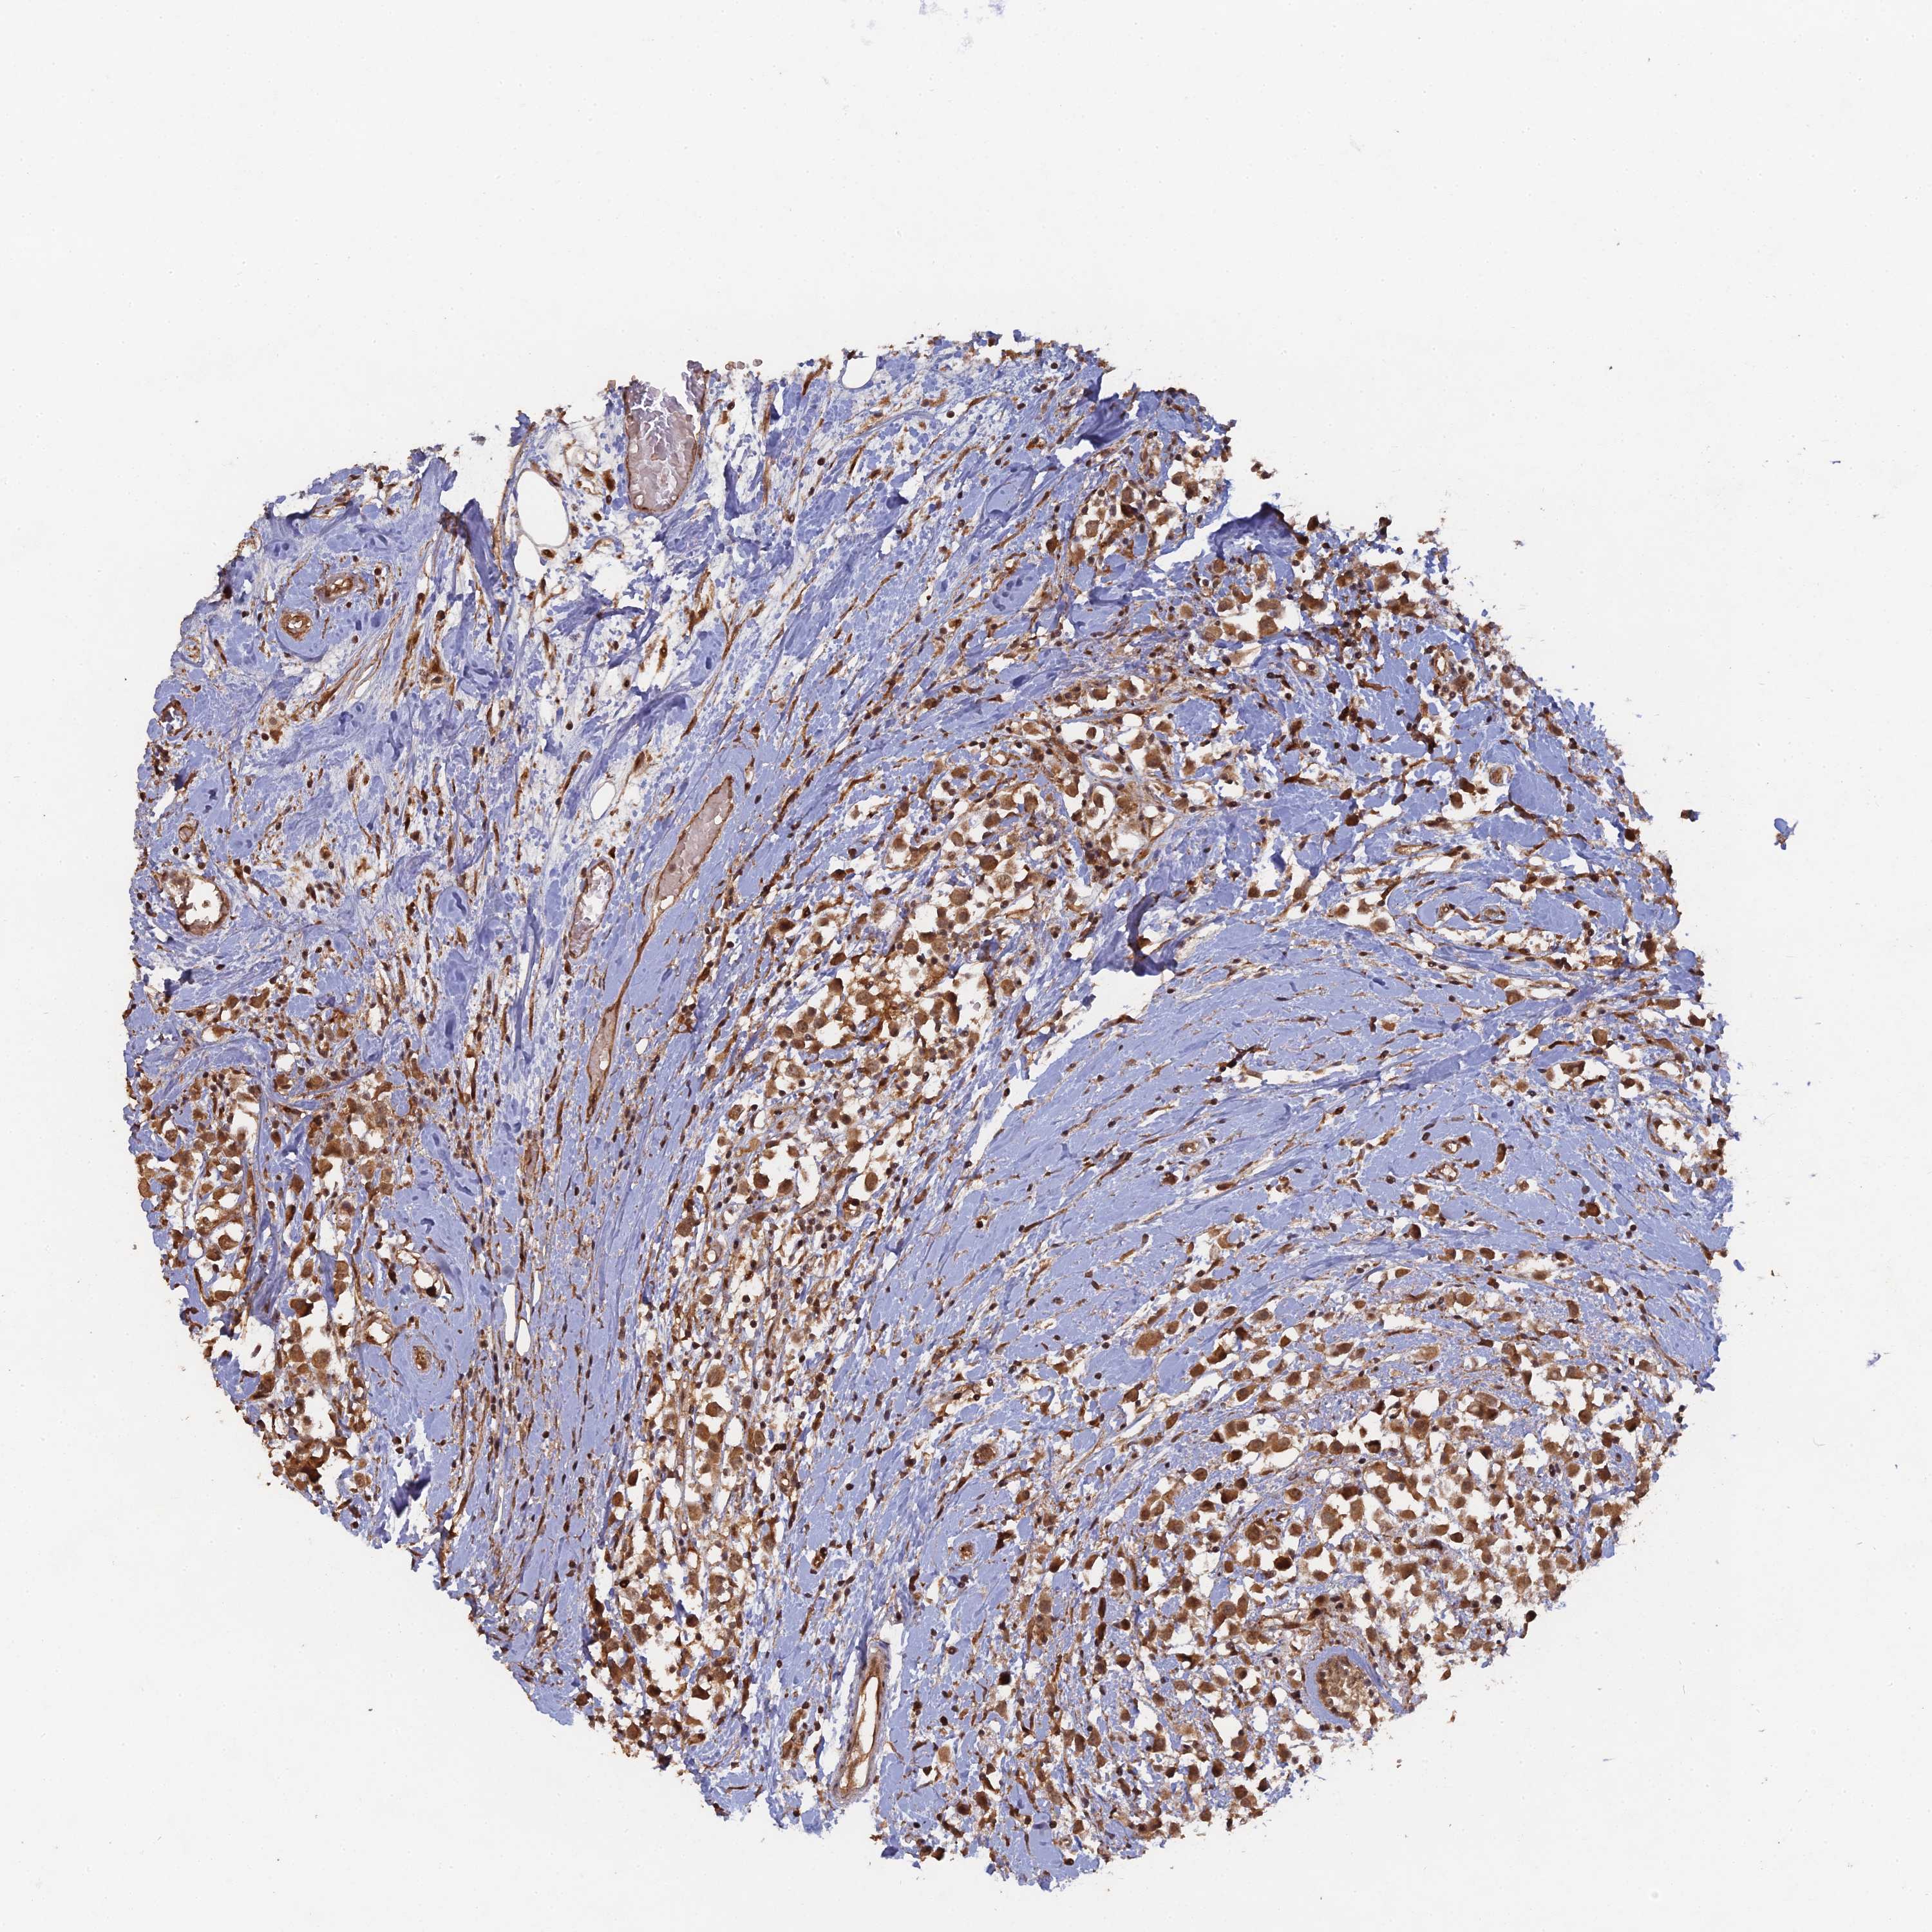

CANCER BREAST CANCER Show tissue menu

BRCA TCGA BRCA VALIDATION PROTEIN EXPRESSION